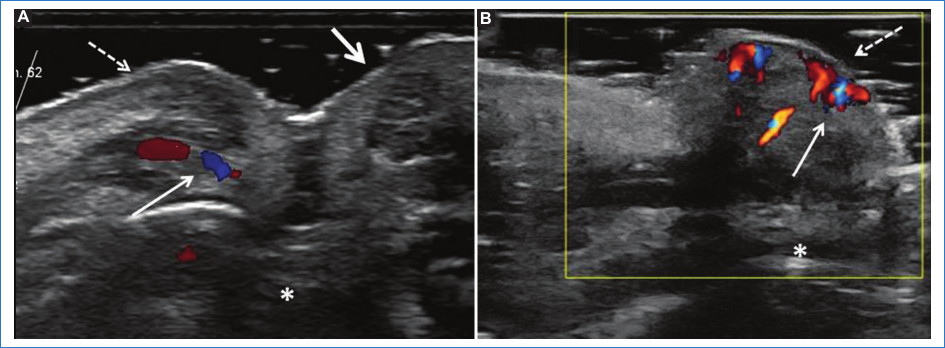

Del grupo 1 (n = 53, 63% del total de pacientes), 51 (96,2%) pacientes eran de sexo femenino y 2 (3,7%) de sexo masculino, 24 (45,2%) no presentaban rellenos previos, 15 (28,3%) presentaban ácido hialurónico (AH) y 14 (26,4%) tenían rellenos permanentes (biopolímeros, silicona y polimetilmetacrilato). Además, 12 (22,6%) pacientes de este grupo presentaron variantes anatómicas, de los cuales solo uno tenía un relleno previo de AH. Entre las variantes encontradas se mencionan arterias angulares, labiales, nasal dorsal y temporal profunda en sitios habituales de inyección de rellenos, glándulas parótidas prominentes y venas intercantales prominentes en sitios de inyección frecuentemente utilizados (Figs. 1, 2 y 3). En este grupo se presentaron 2 (3,7%) pacientes con prótesis faciales. Del total de pacientes que integraron este grupo, el informe ecográfico modificó la conducta del médico estético en el 60% (32) de ellos.

Las técnicas de inyección para la armonización orofacial se basan en “normalidades” anatómicas descritas en la mayor parte de la población. Sin embargo, existen múltiples variantes anatómicas que podrían incrementar el riesgo de complicaciones, ya sea por compromiso vascular (inyección intravascular del material de relleno, compresión vascular extrínseca, etc.), por obtener resultados subóptimos, y hasta que podrían contraindicar alguna técnica específica8. En nuestra población se encontraron 12 variantes anatómicas que condicionaron un cambio en la técnica y/o plano de inyección habitualmente empleado por el médico estético.

Entre estos pacientes hallamos una arteria angular supraperióstica en la fosa piriforme, localización infrecuente. El plano supraperióstico es el sitio de inyección recomendando en los consensos basados en la anatomía más comúnmente hallada; si el médico inyector utilizara esta técnica, tendría mayor riesgo de ocasionar una oclusión arterial8,9.

Un sitio comúnmente utilizado para el relleno en la fosa temporal es a 1 cm lateral y 1 cm por encima del final de la cola de la ceja, en plano supraperióstico. Lee et al.11 han descrito que hasta 1/3 de la población estudiada mediante ecografía Doppler incluida en su trabajo presentaba una arteria temporal profunda coincidente con ese punto habitual de inyección. En nuestro estudio, se evitó dicha técnica de relleno en un paciente que presentaba esta variante vascular.

La inyección de material de relleno en la región nasal, ampliamente conocida como “rinomodelación sin cirugía”, es uno de los procedimientos más riesgosos, ya que una inyección accidental intravascular de la arteria nasal dorsal podría condicionar compromiso de la arteria oftálmica con riesgo de ceguera permanente12. La técnica de inyección de rellenos mayormente utilizada es en el plano supraperióstico y siguiendo la línea media para evitar el compromiso de las arterias nasales dorsales8,13. En nuestro estudio, encontramos a un paciente que presentaba una variante anatómica de las arterias dorsales nasales, con doble arteria nasal dorsal izquierda, y otro paciente con venas intercantales prominentes y supraperiósticas; estas variantes incrementan el riesgo de eventos vasculares no deseados14.

Asimismo, se observaron dos pacientes con una glándula parótida de tamaño muy prominente como variante constitucional (sin signos inflamatorios), que condicionaron un cambio del plano de inyección de rellenos para evitar un depósito intraglandular inadvertido. El depósito de rellenos intraglandulares inadvertidos podría desencadenar posteriormente una inflamación glandular2,15.